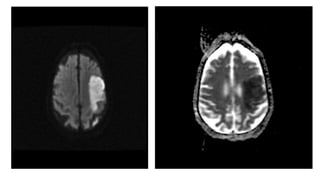

DWI and ADC (diffusion-weighted

imaging and apparent diffusion coefficient)

• These "blocky" images show how easily water moves around

• Restricted diffusion occurs in stroke, abscesses and cellular

tumors

DWI and ADC

• is a commonly performed MRI sequence for evaluation of

acute ischemic stroke, and is sensitive in the detection of small and

early infarcts. Conventional MRI sequences (T1WI, T2WI) may not

demonstrate an infarct for 6 hours, and small infarcts may be hard to

appreciate on CT for days, especially without the benefit of prior

imaging.

• Increased DWI signal in ischemic brain tissue is observed within a few

minutes after arterial occlusion and progresses through a stereotypic

sequence of apparent diffusion coefficient (ADC) reduction, followed

by subsequent increase, pseudo-normalization and, finally, permanent

elevation. Reported sensitivity ranges from 88-100% and specificity

ranges from 86-100%.